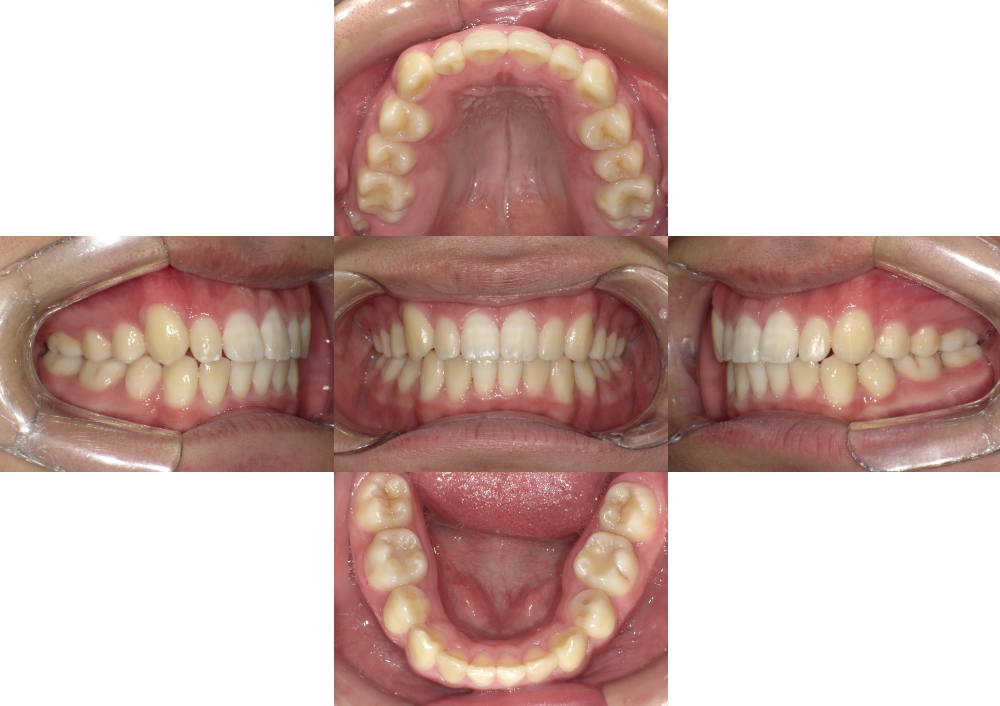

症例写真

AFTER